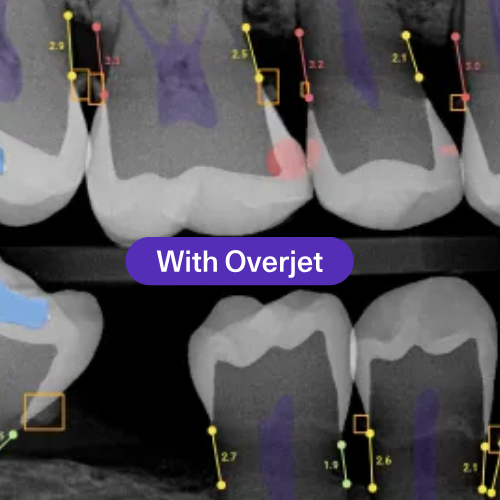

Overjet – x-rays AI ( soon )